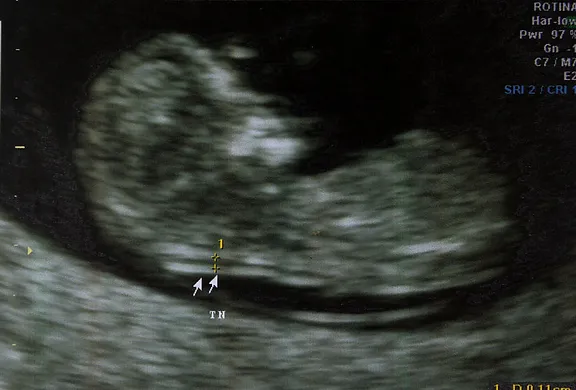

A translucência nucal (TN) é um exame de triagem executado durante o primeiro trimestre da gravidez, por meio de uma ultrassonografia, para medir o acúmulo de líquido na região da nuca do feto. Este exame não fornece um diagnóstico definitivo, mas avalia a probabilidade do feto apresentar certas anomalias cromossômicas, como a Síndrome de Down, Síndrome de Edwards, Síndrome de Patau, entre outras. Devido à sua importância no rastreamento de cromossomopatias, a TN pode oferecer valiosas informações sobre a saúde do feto, bem como orientar futuras decisões médicas para os pais.

Os valores de TN são categorizados como normais ou alterados:

- TN Normal: Menor que 2,5 mm, indicando baixo risco de cromossomopatias.

- TN Alterada: Igual ou superior a 2,5 mm, podendo sugerir um risco aumentado para condições genéticas.

O exame deve ser realizado entre a 11ª e 13ª semanas de gestação, quando o feto possui um tamanho entre 45 e 84 mm. Executado neste período, o exame pode identificar até 95% dos casos de anomalias cromossômicas, como as síndromes mencionadas anteriormente.